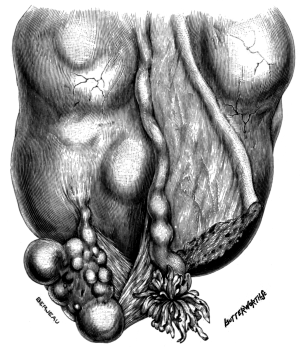

| 30. | Complete Laceration of the Perineum | 127 |

| 31. | Long-handled Sharp-pointed Scissors curved on the flat | 128 |

| 32. | Complete Laceration of the Perineum | 128 |

| 33. | Complete Laceration of the Perineum | 129 |